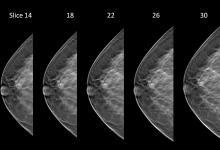

Data from a new study of more than 170,000 examinations using 3-D mammography (breast tomosynthesis) screening technology finds 3-D significantly more invasive cancers than a traditional 2-D mammogram. The researchers also found that 3-D mammography reduces the number of women called back for unnecessary testing due to false alarms. The study was published in the June 25, 2014 issue of the Journal of the American Medical Association (JAMA)

AI is also helping simplify complex tasks and help reduce the reading time on involved exams. One example of this is in 3-D breast tomosythesis with hundreds of images, which is rapidly replacing 2-D mammography, which only produces 4 images. Another example is automated image reconstruction algorithms to significantly reduce manual work. AI also is now being integrated directly into several vendors' imaging systems to speed workflow and improve image quality.